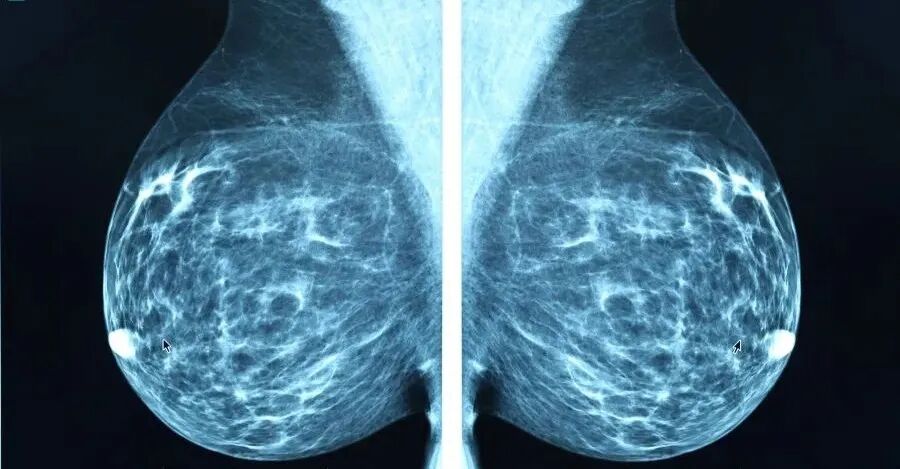

乳腺钼靶(乳腺钼靶X线摄影)是乳腺疾病最基本和首选的影像检查方法,它可以检出临床触诊阴性,也就是医生摸不到的隐匿型早期乳腺癌,尤其在表现为钙化的乳腺癌方面,一些彩超和MRI都难以发现的特定形态的钙化灶,如段样、线样、成簇分布的钙化灶,可能是早期乳腺癌的表现之一。因此乳腺钼靶检查在乳腺癌的早期筛查中有重要作用

看乳腺钼靶检查报告,主要是看结论里面有无肿块影的描述,没有肿块影当然是最好的结果。如果有肿块影但边界较清楚,则良性可能性大;如果边缘有毛刺影,则属于不好的表现,有恶性的可能性。另外就是有无钙化灶的描述,如果是小而模糊,双侧、弥漫散在分布,多为良性表现;如果是钙化排列成线形,或者是集群分布在一个较小的空间内(簇状分布),则考虑为可疑恶性钙化,需进一步活检明确性质。